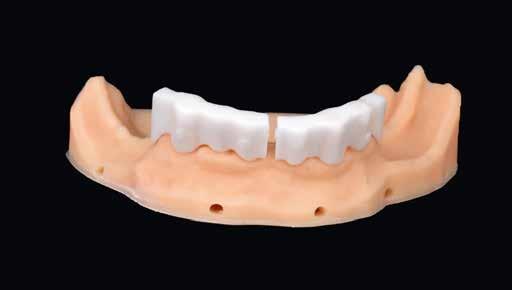

Terápia és implantáció

Az operatív beavatkozás előtt a behelyezett fogsorokkal és azok nélkül is beszkennelték az intraorális szituációt, valamint elkészítették a fogsorok digitális másolatát. Ezután óvatosan kihúzták a maradék fogakat, és mindent előkészítettek az azonnali implantációhoz, amelynek során 6 egyrészes SDS kerámiaimplantátumot terveztek behelyezni a meglévő alveolusba a 34-43 közötti területre. Közvetlenül a behelyezést megelőzően a szék mellett még egyszer megtisztították Diener Denta Plas plazmakészülékkel (lásd 49. kép) az implantátumokat, a lehető legteljesebb csírátlanítás – így a páciens csíraterhelésének minimalizálása – érdekében (2. kép) Az alveolus ózonos tisztítását követően behelyezték a hat egyrészes SDS kerámia-implantátumot, A-PRF (saját vérlemezkében gazdag – a ford.) membránokkal megsegítve. A laborkészítésű előre mintázott elemek alapján azonnali ide-

iglenes került az implantátumokra (3. kép), majd röntgennel újólag ellenőrizték a létrejött helyzetet (4. kép)

nem behatárolt arcelemzés, a fogakat fel lehetett állítani analóg helyzet- és pozícióhelyesen, korrigálva a front kedvezőtlen esztétikáját, meghosszabbítva a felső frontokat (711. képek). A két alsó stég tervezésére a „visszafelé tervezés” (backward-planning – a ford.) elvét alkalmaztuk (12. kép). A stégeket a Vita ultrakemény YZ-T anyagából martuk (13–15. képek). A frézelés közben a virtuális fogpróbát kiegészítettük a műínnyel (16–18. képek). A digitális harapási segédelemeket kinyomtattuk fehér műanyagból 3D nyomtatóval (19–22. képek). A digitális mintákat csak a rendelői ellenőrzés segítségeképpen nyomtattuk ki, mivel remekül szolgálták a stégek biztonságos szállítását és a tervezett restauráció képének bemutatását a megfelelő harapásban (23–29. képek) Az okklúzió minimális korrigálása után összefogták a harapásban a regisztrátumokat, majd a 3D nyomtatású segéd-

elemek visszakerültek a laborba (30. kép). A stégvázak pozícióját szituációs-funkciós lenyomattal rögzítették. A további rendelői fázisokban ellenőrizték az alsó-felső fogpróbákat. Újra kontrollálták az okklúziót, finoman beállították, és újra rögzítették. Következhetett a készrevitel.

A kívánalmak szerint alul teleszkópos, cirkónium-dioxid stégre támaszkodó PEEK-vázas fogsor, felül teljes kivehető lemezes PMMA-fogsor készült.